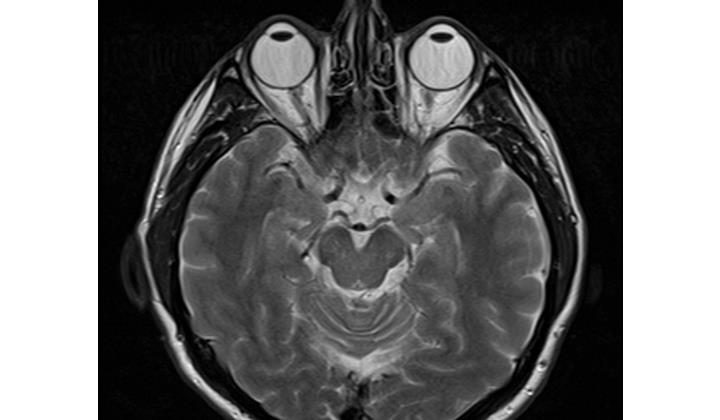

Проведённое исследование, которое опубликовано в журнале Brain Imaging and Behavior, наглядно показало, что нарушения функции мозга непосредственно связаны с тяжестью симптомов обоих расстройств. При этом они могут быть полезны при разработке очередных способов лечения.

«Это аномалии мозга. Мы лечим их с помощью психотерапии или препаратов. Но для успешного результата необходимы именно изменения в мозге», — говорит доктор Уэсли Керр, невролог и исследователь биостатистики Калифорнийского университета в Лос-Анджелесе.